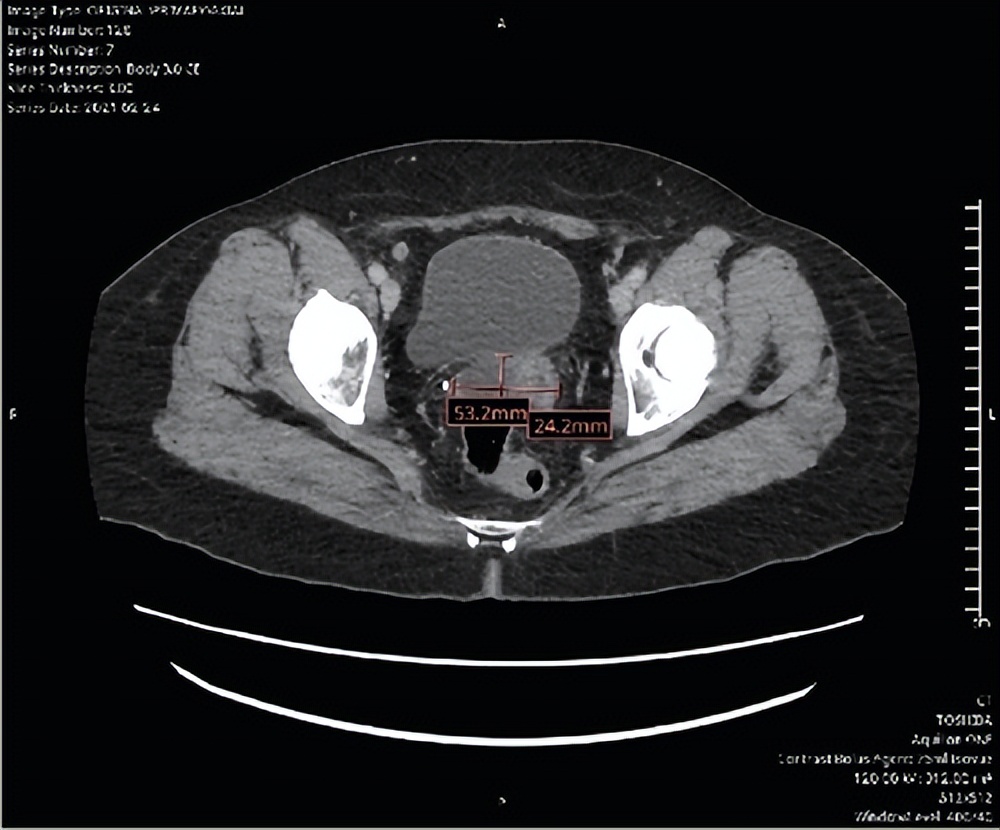

随后,患者接受了三个周期的卡铂联合紫杉醇化疗,之后由于持续存在2级神经病变(尽管已减少紫杉醇剂量),后续接受了三个周期的卡铂单药化疗。患者的CA-125在整个治疗过程中呈下降趋势(图2),完成初次化疗时降至9.5,六个周期结束时的CT扫描显示无疾病证据。患者无疾病状态持续了3年。之后,患者因右上腹疼痛再次就诊于急诊科。CT扫描显示盆腔内紧邻膀胱后壁有一个最大径达5.1厘米的巨大复杂性低密度囊性病灶(图3),以及肝右叶一个亚厘米级结节,总体考虑为恶性肿瘤复发。后续的PET扫描支持这些发现,又发现了腹直肌结节和盆腔结节。治疗团队计划进行手术减瘤。

图3:复发时的CT扫描。轴位图像显示5.3厘米×2.4厘米的复杂性低密度囊性病灶。